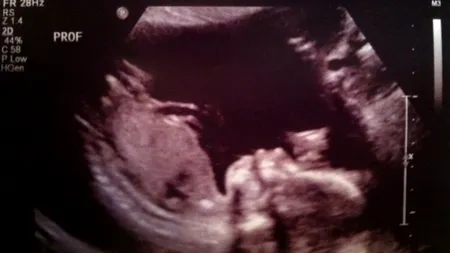

O viitoare mămică s-a dus să facă o ecografie, dar a rămas șocată când a văzut ce era lângă bebeluș